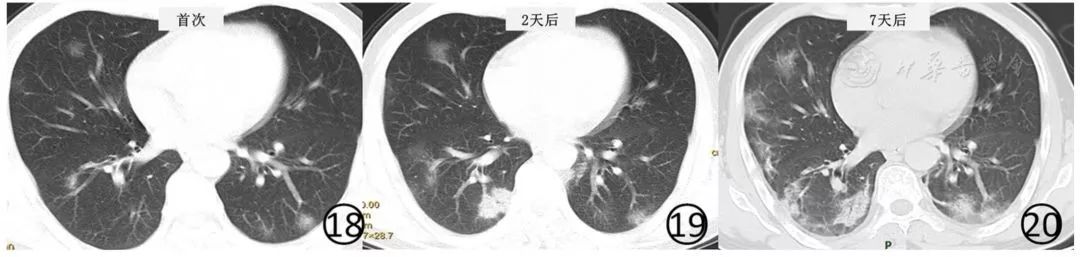

原有磨玻璃阴影或实变影也可融合或部分吸收,融合后病变范围和形态常发生变化,不完全沿支气管血管束分布(图18,图19,图20)。

图18~20 男,46岁。基线(图18)CT平扫显示两肺多发淡薄的磨玻璃阴影,左下肺有结节,周围有晕征,病变位于胸膜下。2d后(图19)及7d后(图20)CT平扫显示病变范围不断扩大,出现新病灶,右下肺实变阴影内有支气管充气征